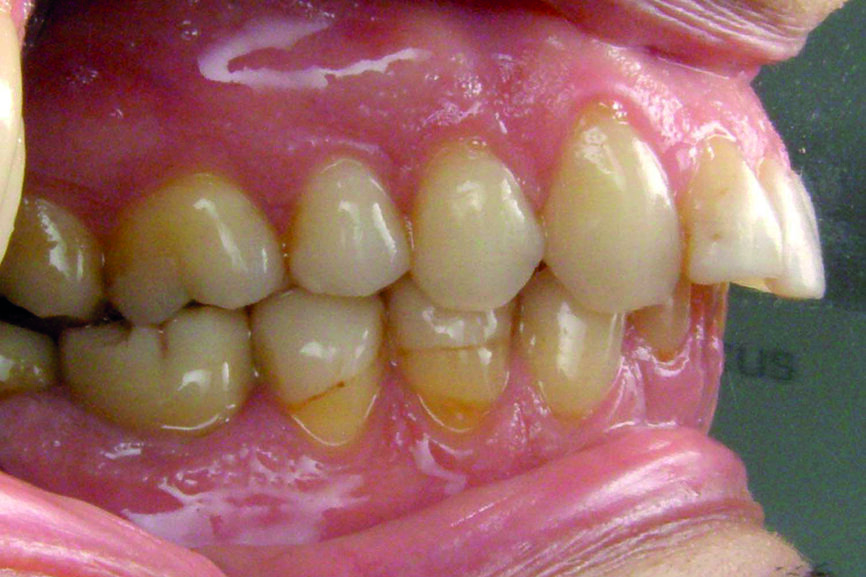

D’un point de vue dentaire le patient présente une Classe II division 1, avec une classe II molaire complète et une classe II canine.

- Présence d’un overjet et d’une supraclusion résiduelle.

- L’arcade supérieure est régulière mais les incisives sont en vestibulo version importante.

- L’arcade inférieure présente un encombrement dans le secteur antérieur associé à une version vestibulaire.

- Les milieux correspondent.